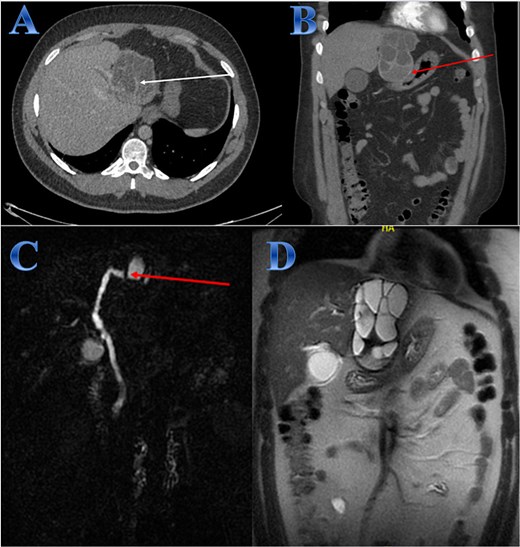

A 31-year-old male presented with a 5-days history of epigastric pain accompanied by jaundice, darkened urine, together with a clay stool. On examination, there was jaundice with epigastric tenderness. Clinical tests showed increased total and direct bilirubin levels. CT showed left hepatic lobe exophytic CE (Fig. 4).

Case 4. (A & B) Post-contrast CT cuts showing well-defined cystic lesion showing internal daughter cysts noted at the left hepatic lobe and seen exophytic indenting the lesser curvature of the stomach, septate lesion is seen in the left lobe of the liver (photo A). The lesion is abutting the lesser curvature of the stomach with intact fat planes between the two (photo A). (C & D) MRI cuts showing well-defined, septate lesion, abutting the lesser curvature of the stomach. The lesion makes some mass effect off the left hepatic biliary radicles communicating with the lesion (photo C).

The patient underwent ERCP for biliary drainage. Subsequent follow-up revealed improved jaundice and reduced pain; at that time, the patient was started on albendazole, which continued for 2 months. The patient was admitted for surgery, and laparoscopic left lateral resection was done. After liver mobilization was done by detaching the falciform, left triangular and coronary ligaments to mobilize the left liver lobe. Retraction of the left lateral segment was performed to expose segments 2 and 3 which were isolated using laparoscopic gauze soaked in hypertonic saline A harmonic scalpel was used for parenchyma transection, and the left bile duct was identified between segments 4 and 2 and 3, which was transected using endovascular gastrointestinal stabler (endo-GIA). Before ending the parenchyma dissection upward, the left hepatic vein was identified and divided using endo-GIA (Fig. 4).